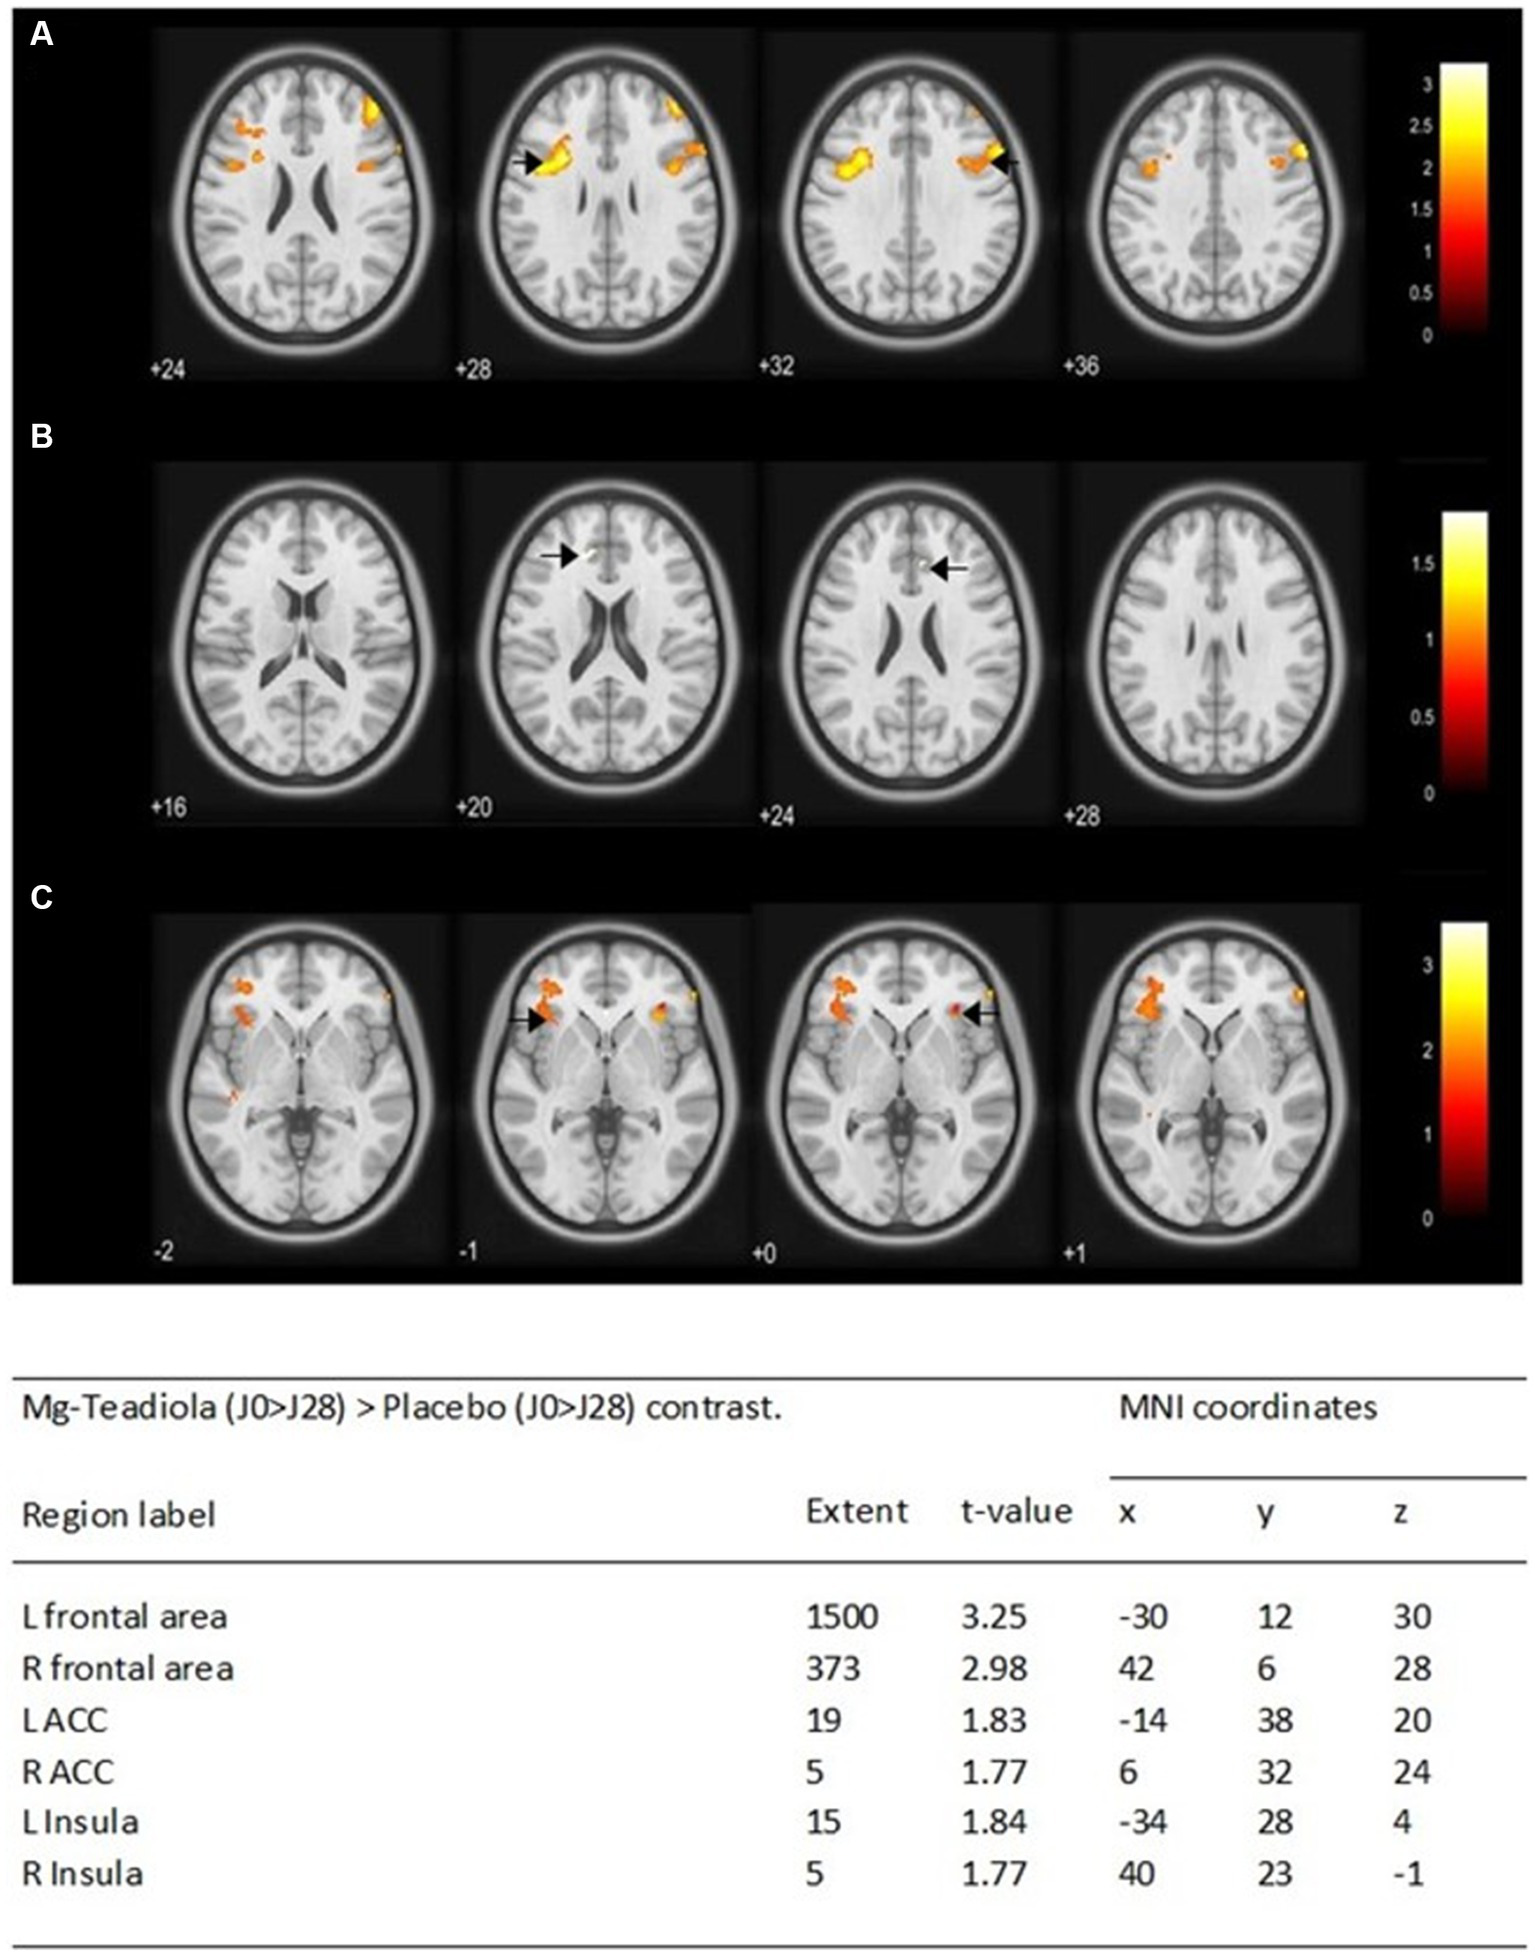

Comparison of BOLD signal variations between D0 and D28 (D0 > D28) during stress stimulation between Mg-Teadiola versus placebo groups showed significantly increased activations in the left and right frontal area (p = 0.001 and p = 0.002, respectively), the left and right ACC (p = 0.035 and p = 0.04, respectively), and the left and right insula (p = 0.034 and p = 0.0402, respectively) (Figure 5).

Figure 5. Whole-brain analysis of the blood-oxygen-level-dependent (BOLD) responses of the Mg-Teadiola (D0 > D28) > Placebo (D0 > D28) contrast during stress stimulation Statistical t maps were overlaid on MNI slices using a voxel-wise threshold of p < 0.05 and an extent threshold of five voxels. They were covering frontal area (A), ACC (B), and insula (C). Black arrow points each region of interest at L and R. Regions were automatically labeled using the Anatomy Toolbox atlas of SPM and were presented in the table below. x, y, and z were MNI coordinates in the L-R, anterior–posterior, and inferior–superior dimensions, respectively. All peaks were significant at a voxel-wise threshold of p < 0.05 (extend threshold = 5 voxels). ACC, anterior cingulate cortex; L, left; R, right; MNI, Montreal Neurological Institute; SPM, Statistical Parametric Mapping.